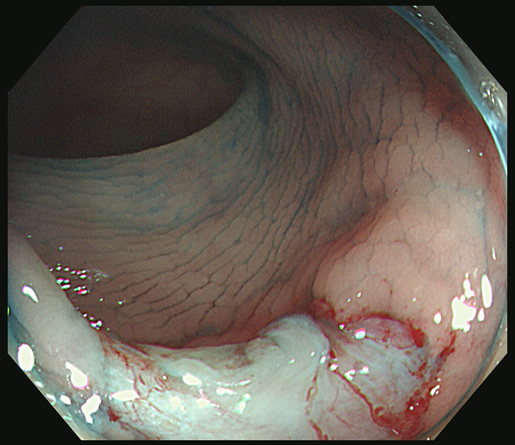

「Extended Cold法」で切除し、切除創を詳細に観察することが肝要です

「遺残の可能性」がわずかでもある場合は、「辺縁のトリミング」を追加します

患者さんは、「ポリープ切除後の写真」をしっかり確認することが重要です。